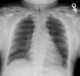

Hunter syndrome, or mucopolysaccharidosis type II (MPS II), is a rare genetic disorder in which large sugar molecules called glycosaminoglycans (or GAGs or mucopolysaccharides) build up in body tissues. It is a form of lysosomal storage disease. [Source: Wikipedia ]